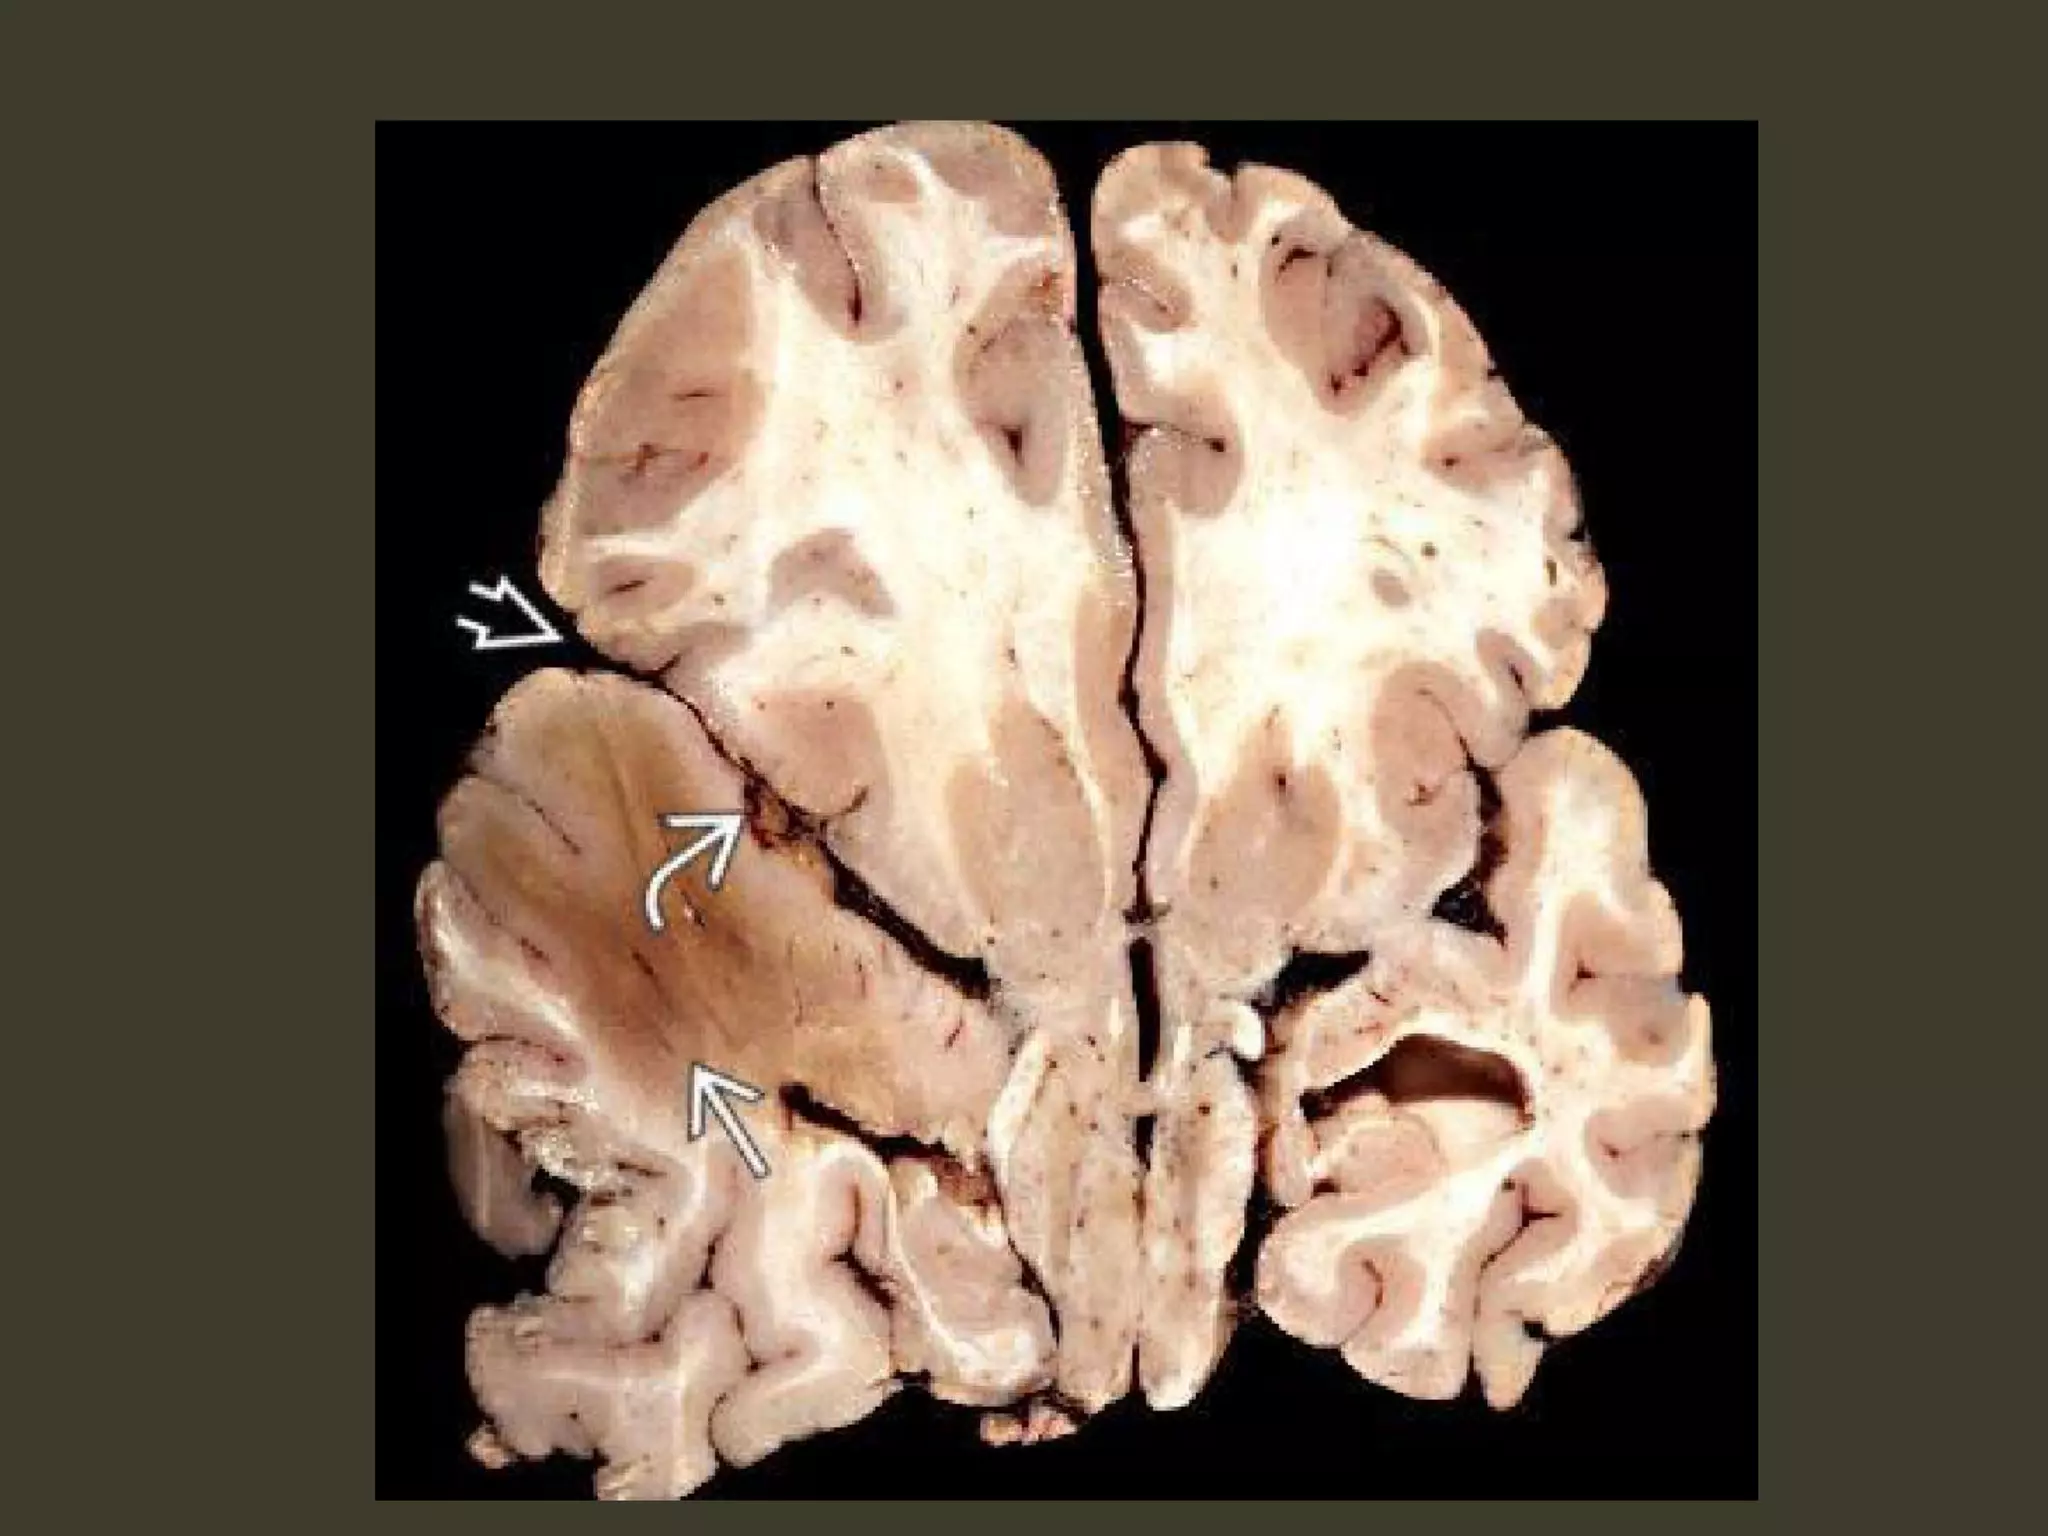

Duret hemorrhage

"Top-down" mass effect displaces the midbrain

inferiorly

closes the midbrain-pontine angle

Perforating arteries from basilar artery

are compressed and buckled

hypothalamic and basal

ganglia infarcts

complete bilateral DTH

perforating arteries from the

circle of Willis compression against the

central skull base

hypothalamic and basal ganglia

infarcts